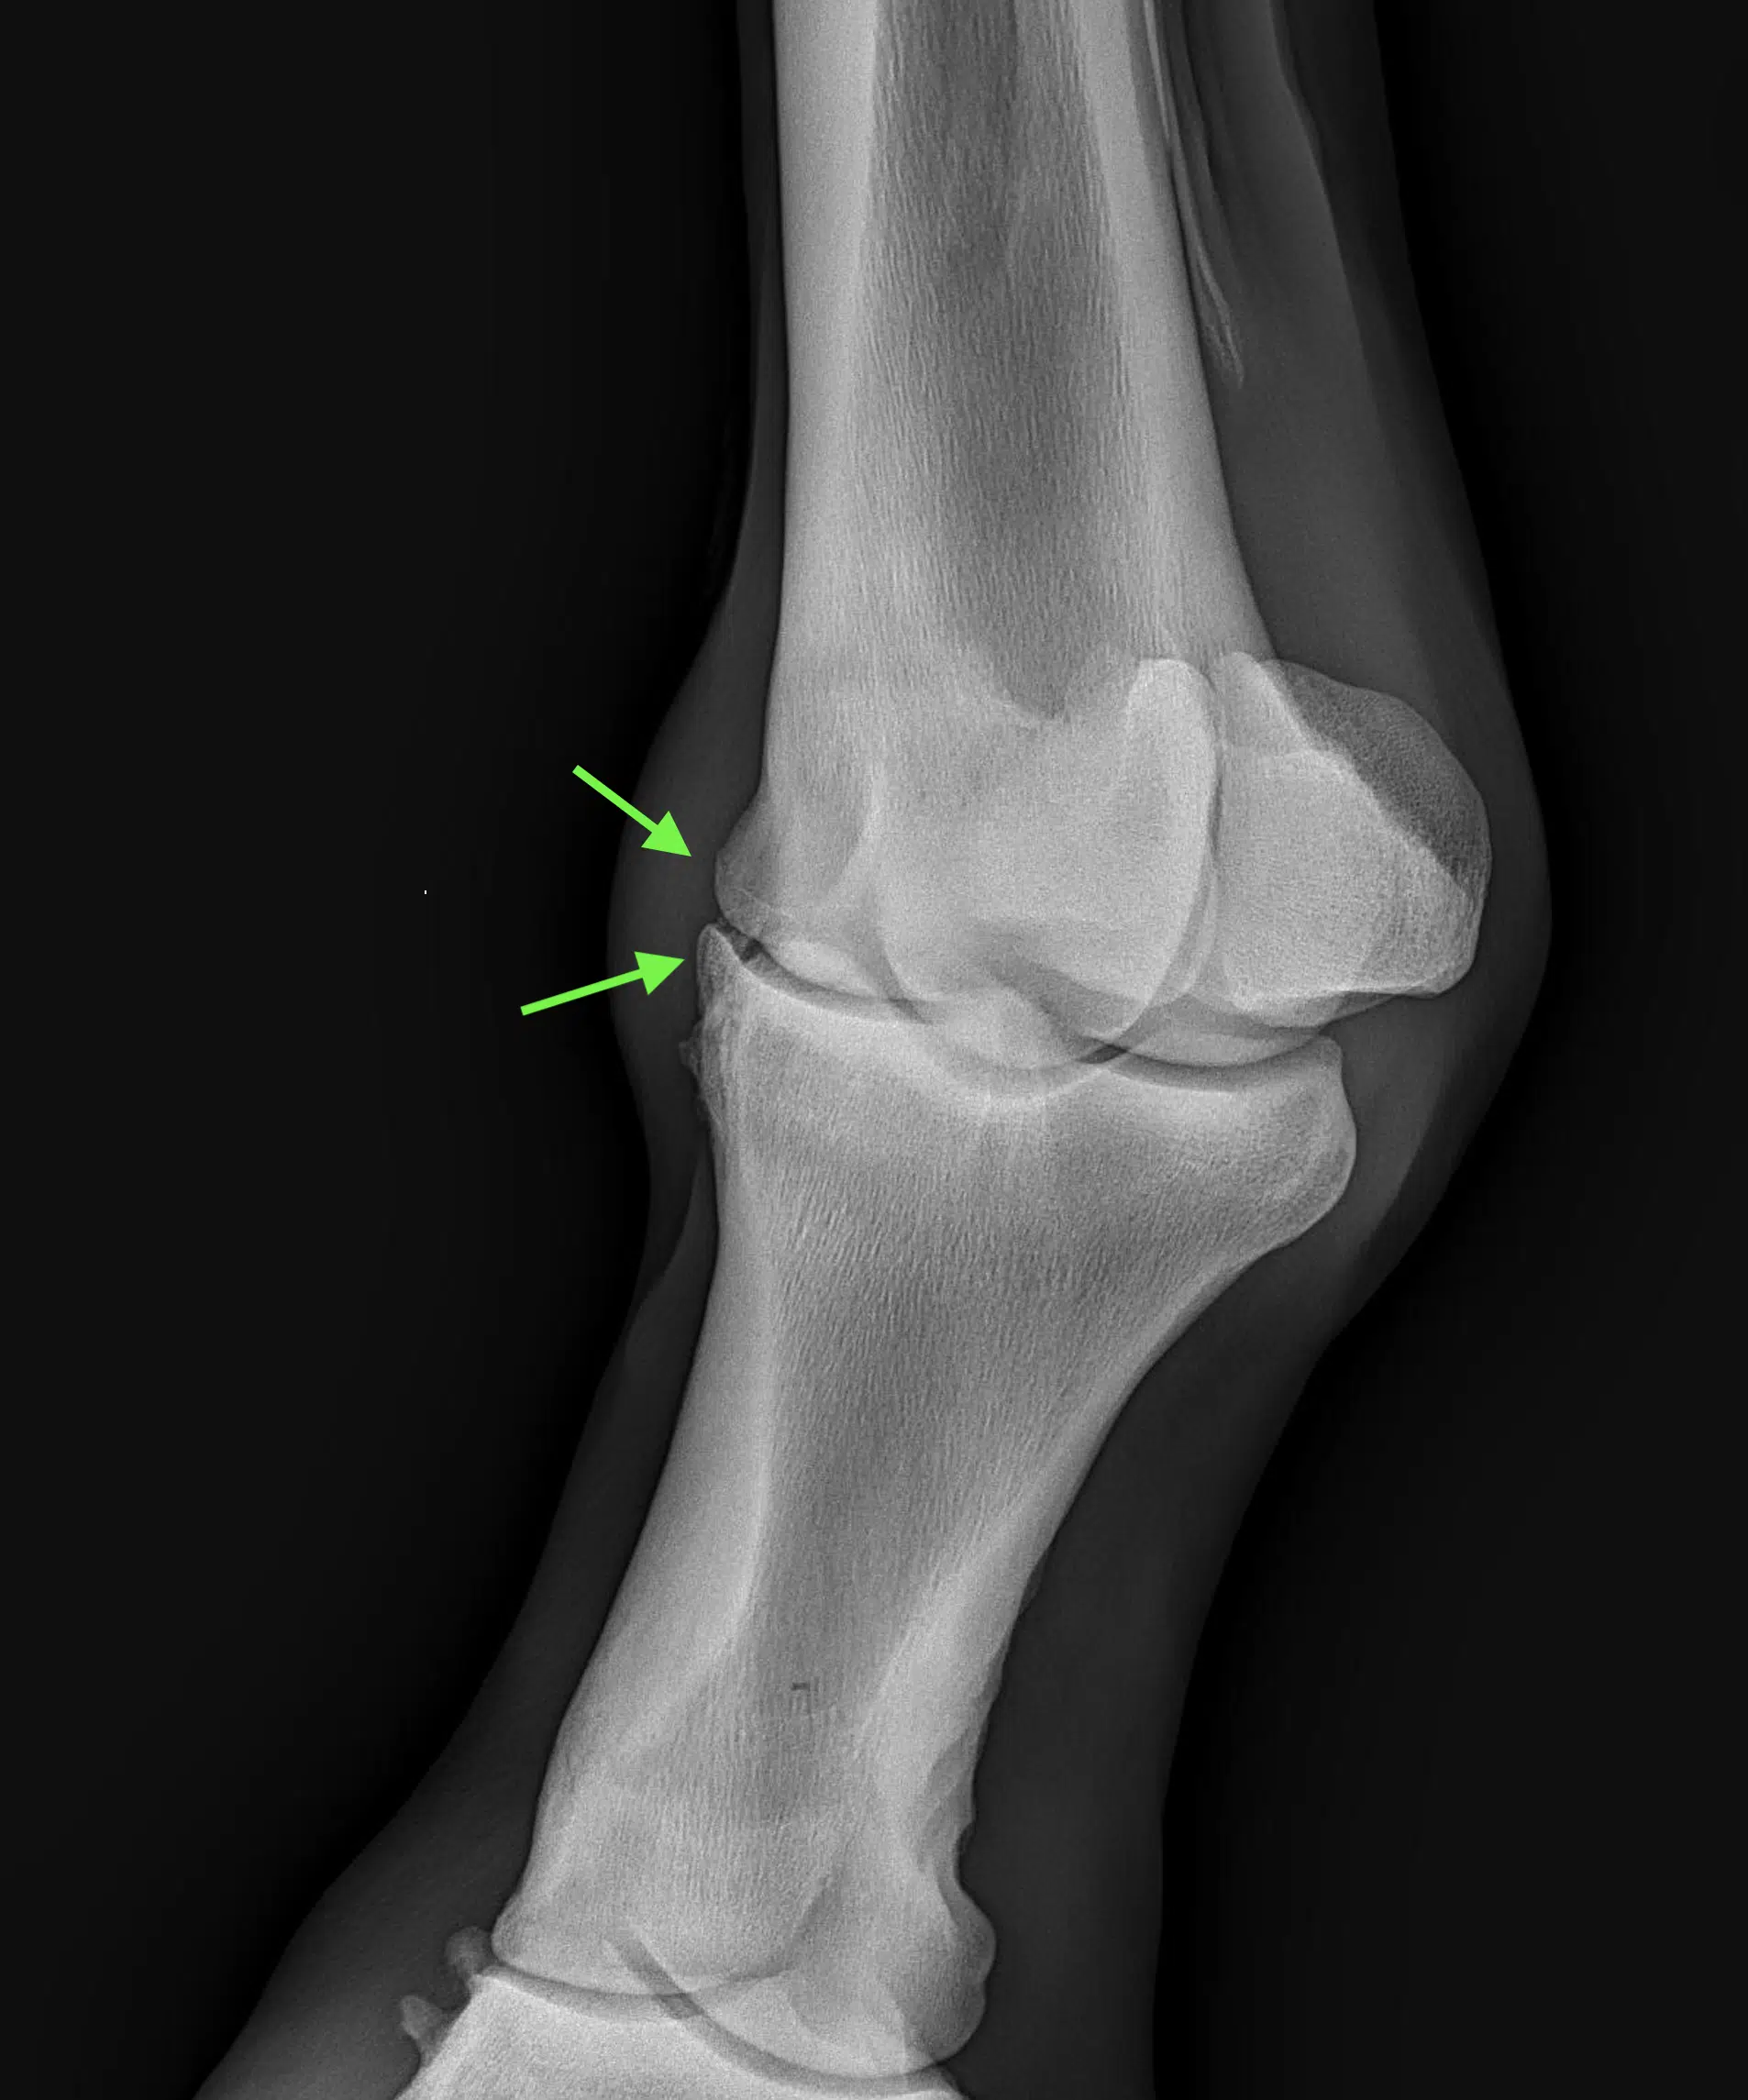

2.4. Subchondral bone disease

the subchondral bone is located deep to the articular cartilage and is highly responsive to loading. Subchondral bone disease is a term that describes the different phases and spectrum of pathologic changes observed within the subchondral bone when the bone does not have the opportunity to appropriately complete the repair processes that take place in response to repetitive loading through the normal adaptive process of bone modeling (geometric sculpting of bone by formation and/or resorption) and remodeling (damaged bone is resorbed by osteoclasts, followed by recruitment of osteoblasts to replace the removed bone).

Cause:

(all joint diseases): repetitive or acute exercise-induced overload in combination with altered biomechanics and impaired shock absorption leading to increased strain on the joints.

Effects of Twin Shoes:

protective effect (reducing stress) on the joint and surrounding structures by:

– maintaining normal distal limb joint angulation by allowing a normal functioning hoof mechanism (heel movement and sagittal flexibility),

- maintaining medio-lateral joint balance on circles and on uneven surface by allowing a normal functioning hoof mechanism (lateral flexibility),

– maintaining natural shock absorption capacity of the hoof by allowing a normal functioning hoof mechanism (heel movement) and circulation and

– maintaining hoof angle between shoeing cycles due to more equal hoof wear of toe & heels.